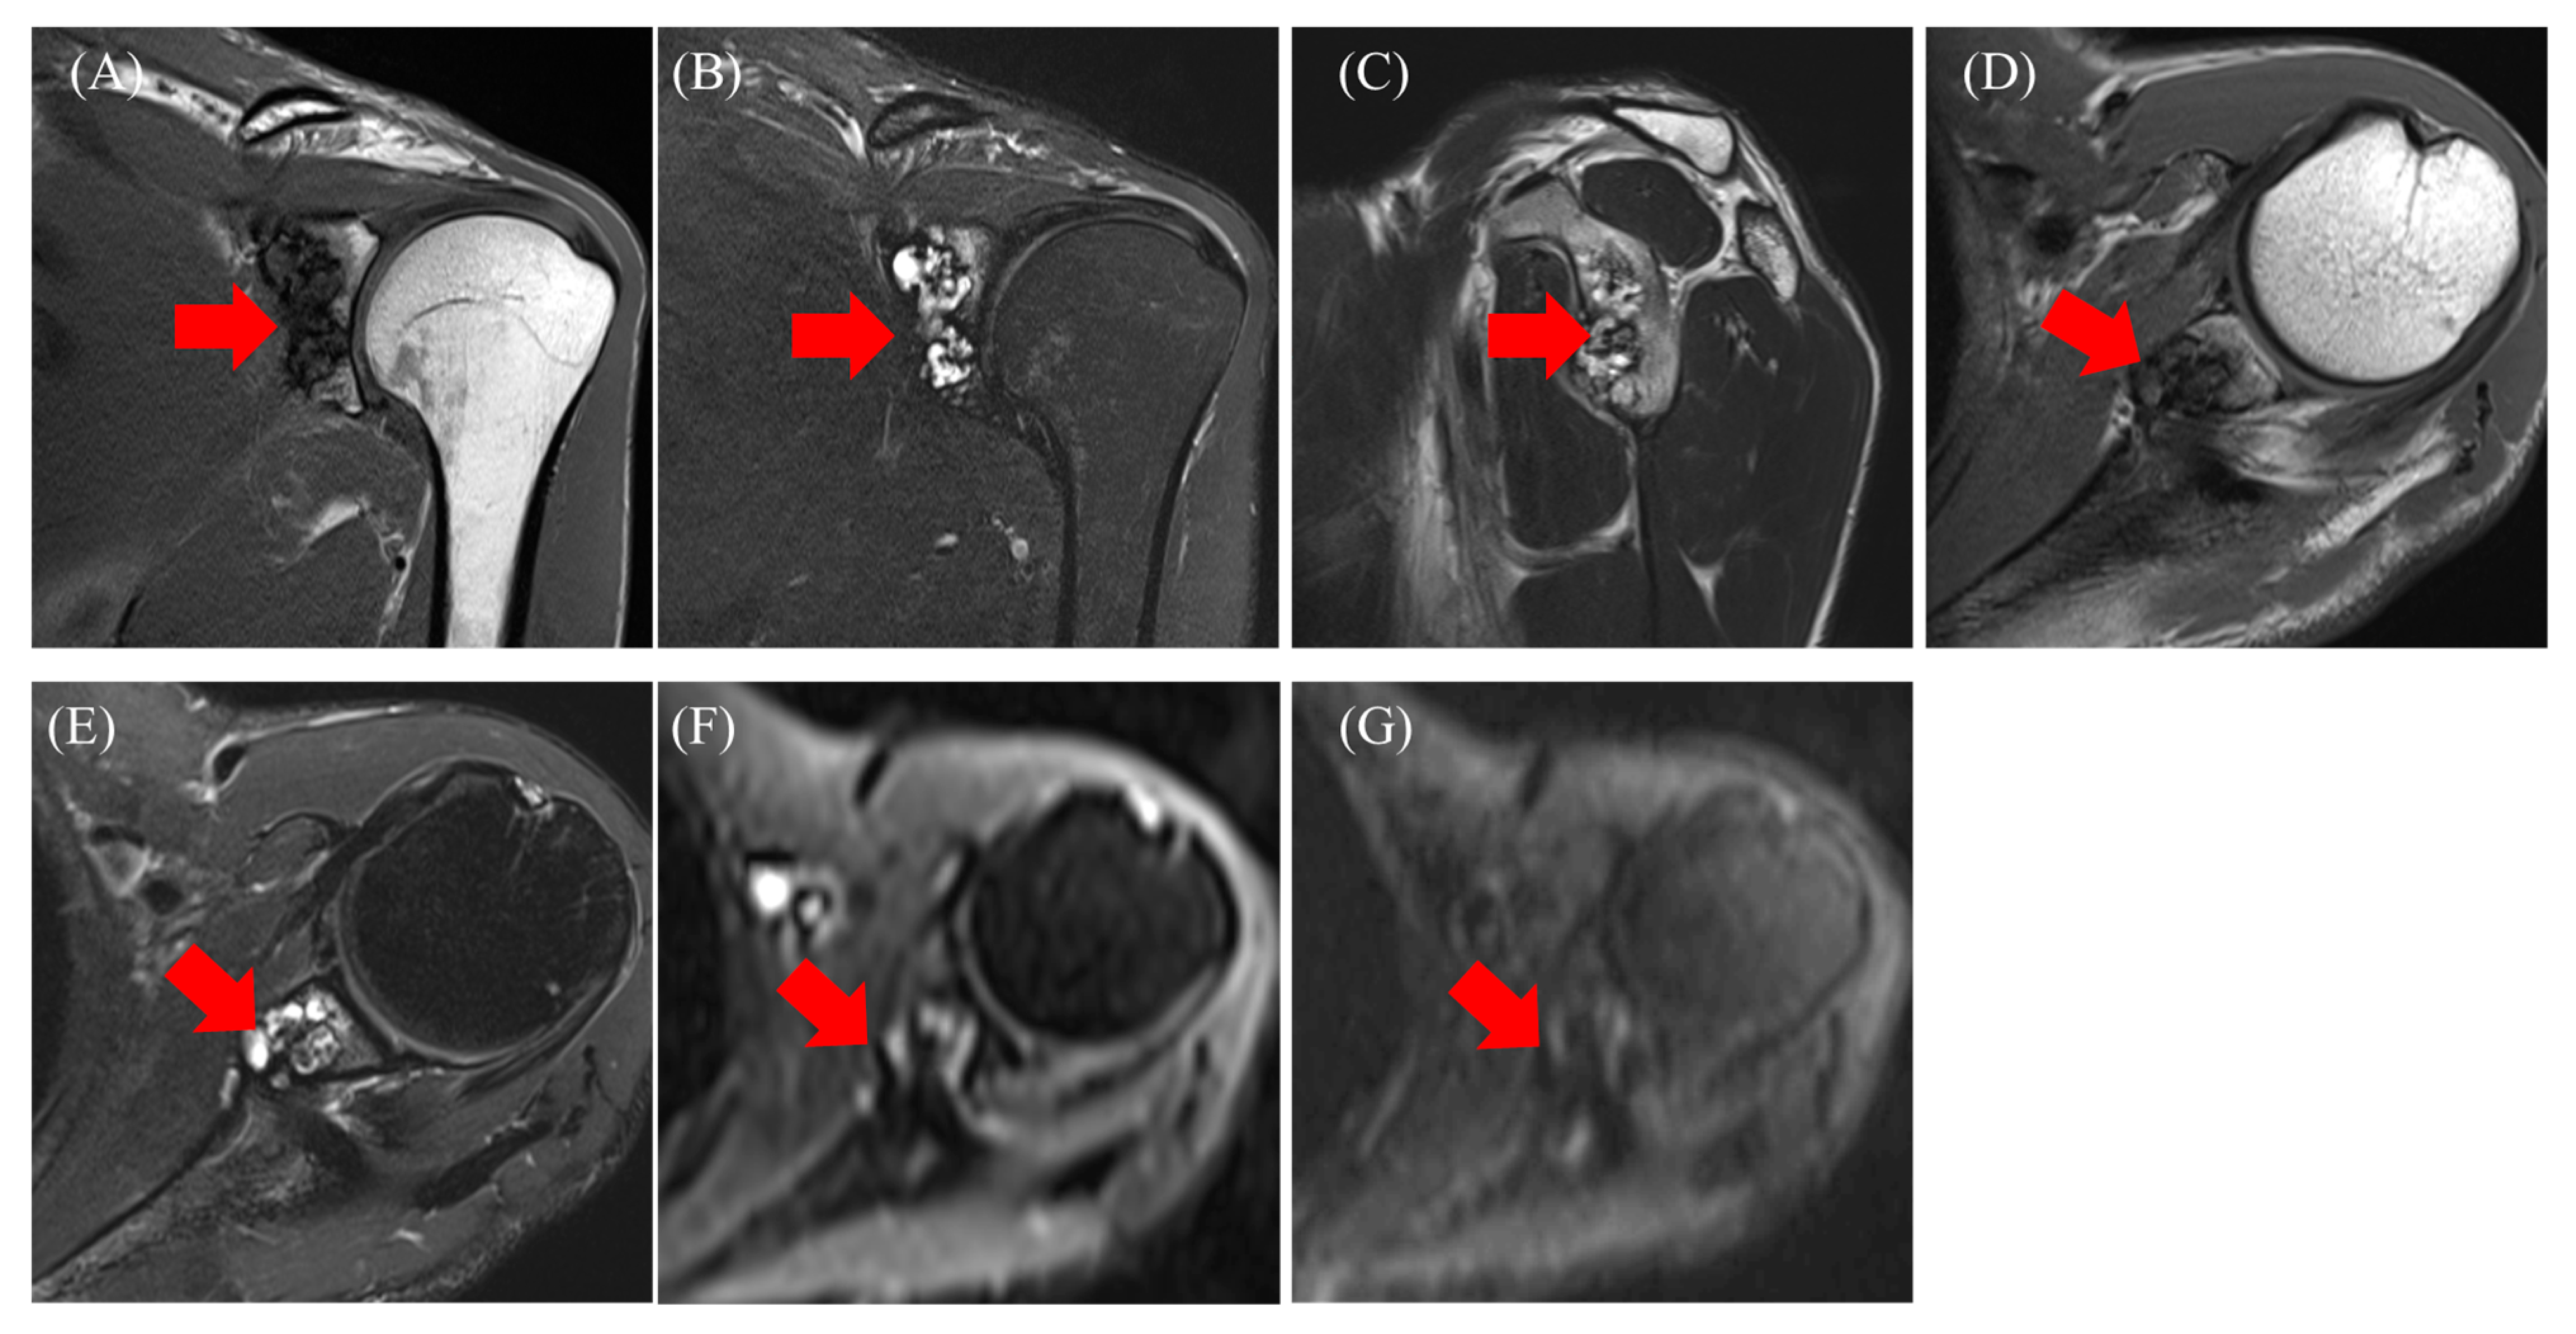

2.1. Case 1